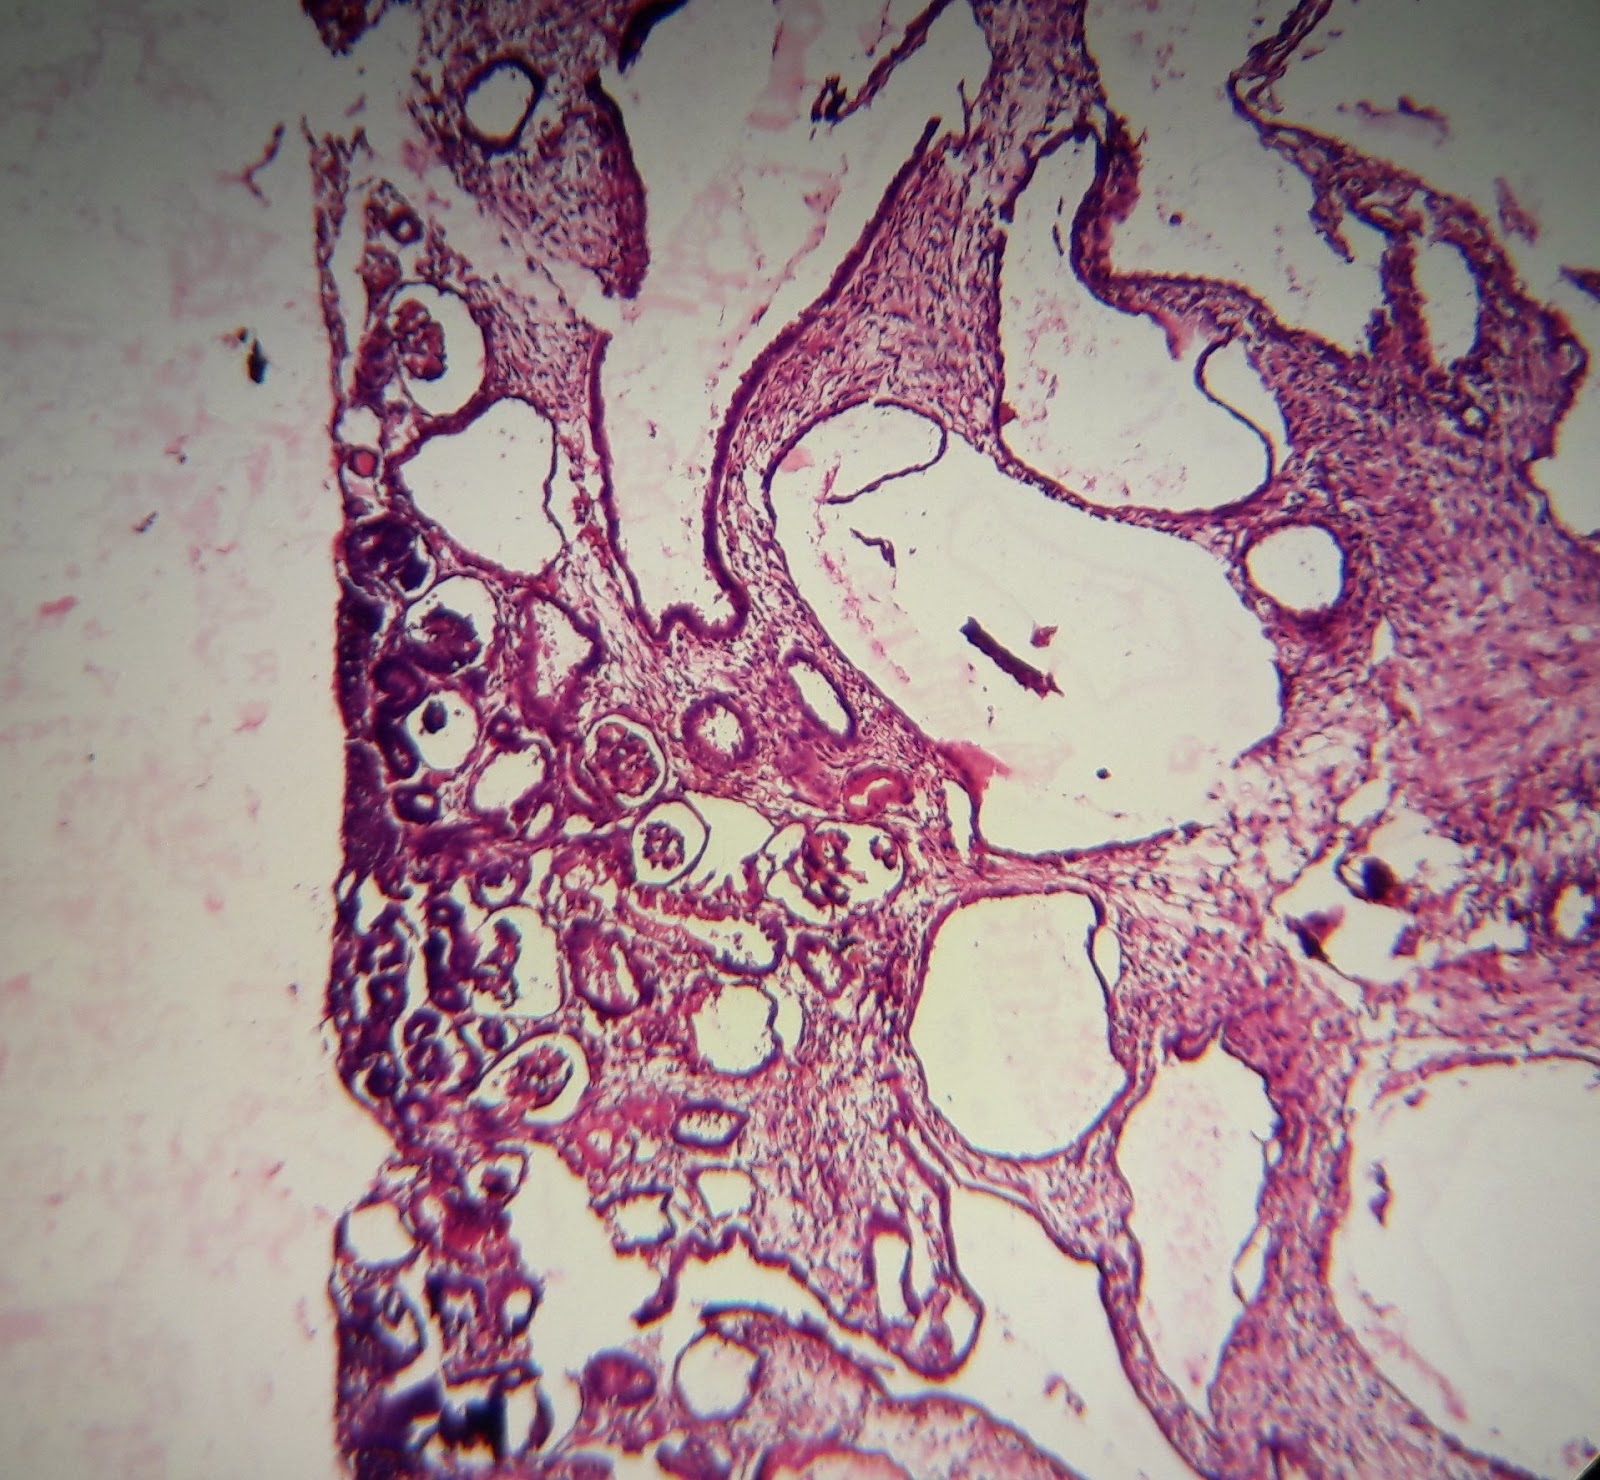

Intraepithelial neoplasia

Low grade PIN

Only nuclear hyperchromasia

High grade PIN

Nucleoli visible at 20X (> 1 μm). May show architectural features like cribriform/ tufted/ micropapillary.

| Intraepithelial neoplasia - cribriform |